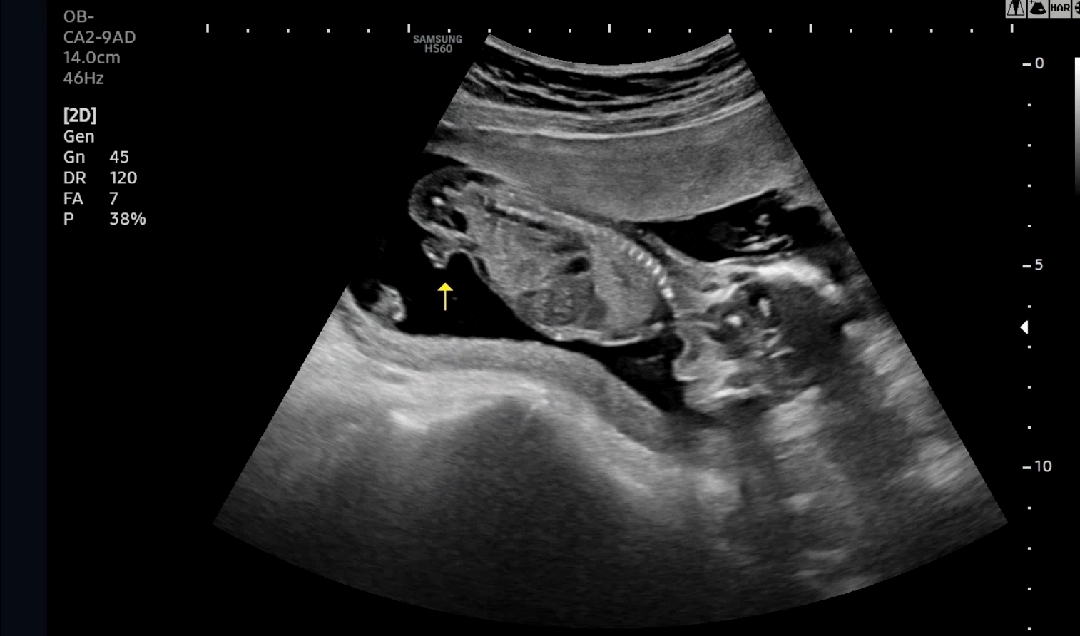

16주차 초음파예요. 아들 맞나요~? 딸인데 이렇게 보일리는 없겠죠...? 나왔다가 들어갈일도 없겠죠? ㅎㅎㅎ